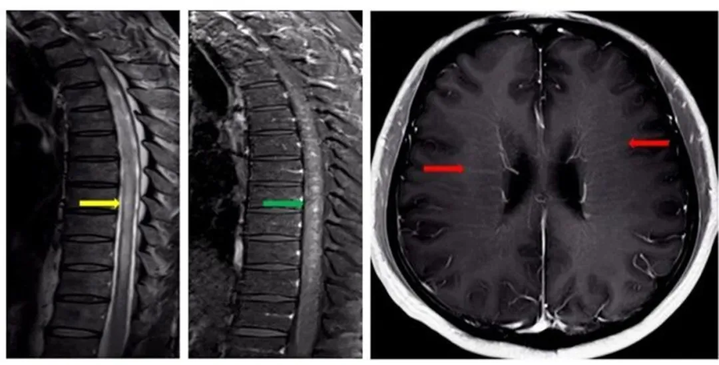

时建铨给陈老师安排了脊髓+头颅增强核磁共振检查,结果提示:脊髓长节段异常信号(图1中黄色箭头)伴斑片状强化(图1中绿色箭头),且脑室周围存在线样放射状强化(图1中红色箭头)。

根据影像学表现,结合陈老师不断加重的症状,符合亚急性进展性病程,经验丰富的时建铨脑海中顿时闪现出一种疾病——自身免疫性胶质纤维酸性蛋白(GFAP)星形胶质细胞病。

3.典型影像学特征:头颅核磁共振检查显示脑室周围线样放射状强化;脊髓核磁共振检查显示颈胸段脊髓长节段异常信号伴斑片状强化。